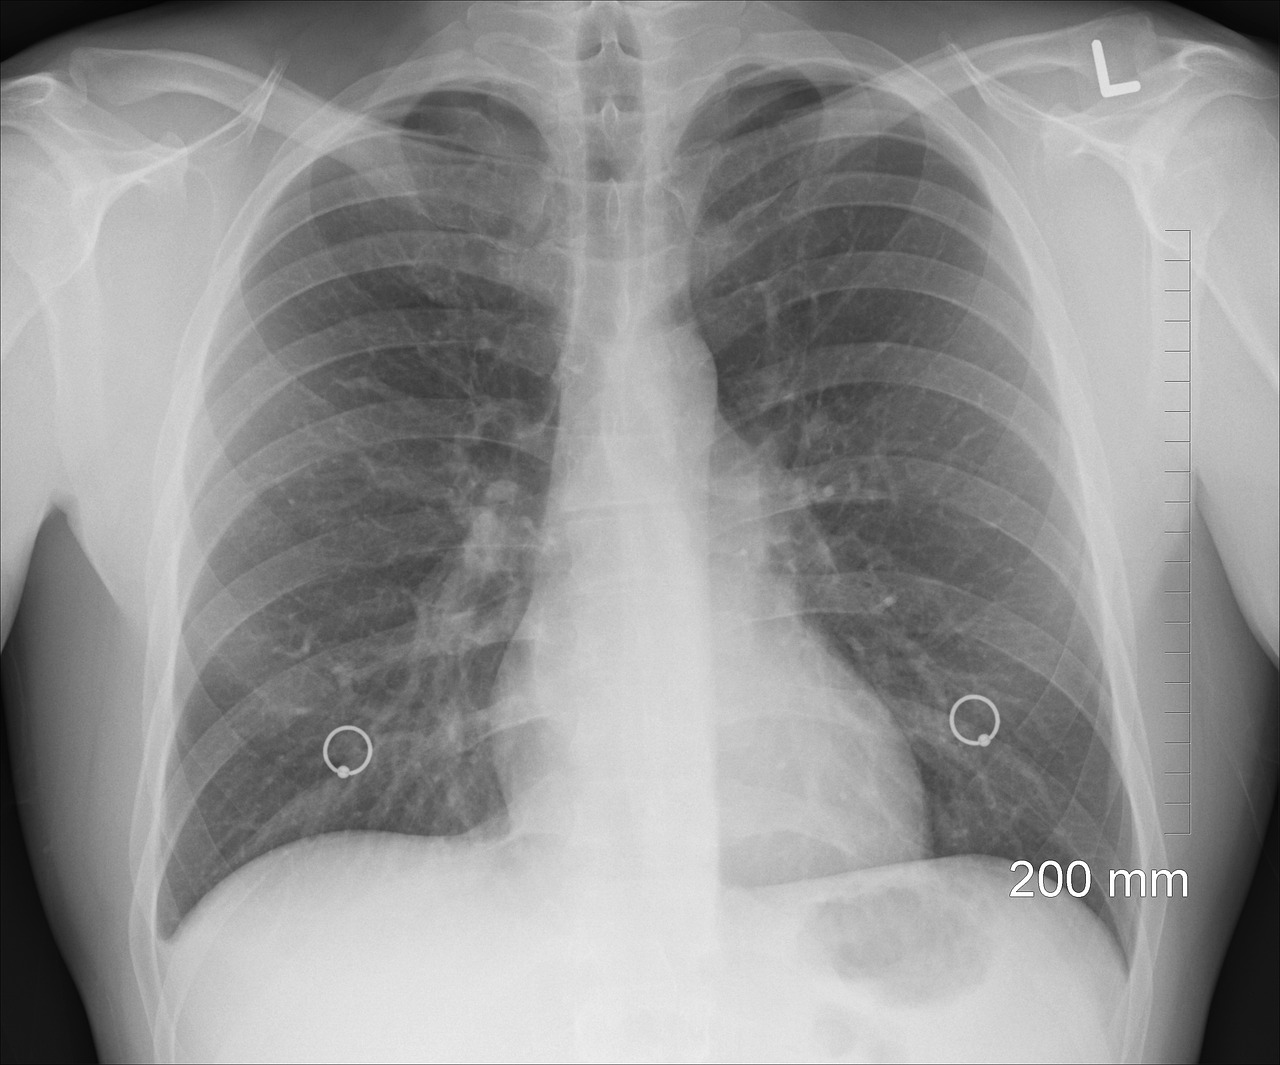

Dia Mundial do Pulmão: Sociedades médicas pressionam criação de rastreio ao cancro do pulmão

Oito sociedades médicas e outras instituições da área da saúde juntaram-se num documento com recomendações para pressionar a criação de um rastreio nacional ao cancro do pulmão, a neoplasia que mais mata em Portugal, e que será hoje apresentado.

António Morais lembrou que as tentativas de programas de rastreio com radiografia “nunca mostraram evidência do seu benefício” e explicou que, recentemente, o rastreio com TAC (Tomografia Computorizada) de baixa dose “mostrou um benefício significativo, com deteção precoce de lesões”, o que levou, nalguns casos, a uma diminuição da mortalidade em 20 a 25%.